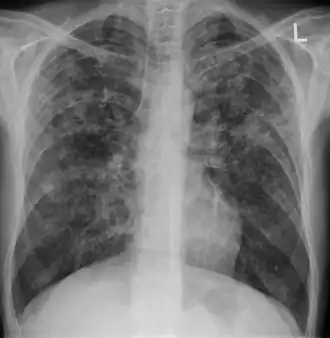

| Chest X ray showing miliary tuberculosis | |

Miliary tuberculosis is a form of tuberculosis that is characterized by a wide dissemination into the human body and by the tiny size of the lesions (1–5 mm). Its name comes from a distinctive pattern seen on a chest radiograph of many tiny spots distributed throughout the lung fields with the appearance similar to millet seeds—thus the term "miliary" tuberculosis. Miliary TB may infect any number of organs, including the lungs, liver, and spleen.[2]

Testing for miliary tuberculosis is conducted in a similar manner as for other forms of tuberculosis, although a number of tests must be conducted on a patient to confirm diagnosis.[3] Tests include chest x-ray, sputum culture, bronchoscopy, open lung biopsy, head CT/MRI, blood cultures, fundoscopy, and electrocardiography.[9] The tuberculosis (TB) blood test, also called an Interferon Gamma Release Assay or IGRA, is a way to diagnose latent TB. A variety of neurological complications have been noted in miliary tuberculosis patients—tuberculous meningitis and cerebral tuberculomas being the most frequent. However, a majority of patients improve following antituberculous treatment. Rarely lymphangitic spread of lung cancer could mimic miliary pattern of tuberculosis on regular chest X-ray. [14]

X-ray, 13 days after onset, showing bilateral interstitial infiltrates -

X-ray, 22 days after onset, showing extensive bilateral reticulo-nodular infiltrates -